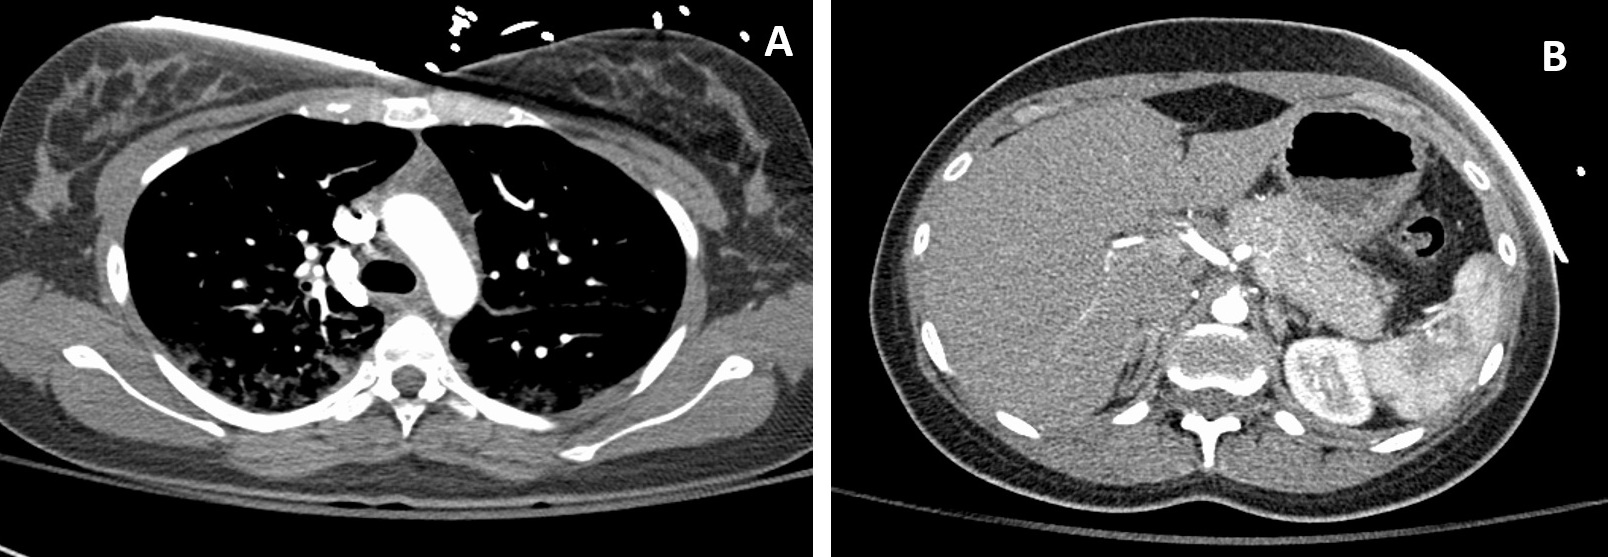

The thymic gland and pancreas were also prominent on the scans, suggestive of thymic hyperplasia and autoimmune pancreatitis, respectively, hence our rationale for evaluating her IgG-4 levels (Figure 2). During this time, the patient began displaying new vertical nystagmus. A magnetic resonance imaging (MRI) scan of the brain illustrated small areas of abnormal signaling in the right frontal lobe (Figure 3). The patient was transferred to the critical care unit for further management and was stabilized with intravenous fluids and antibiotics including azithromycin, 500 mg, daily and ceftriaxone, 1 mg, daily for 5 days.

Figure 2. A computed tomography scan showed prominence of the thymic gland, presumably because of thymic hyperplasia (A). Prominence of the pancreas was also noted, with loss of interdigitations (B).